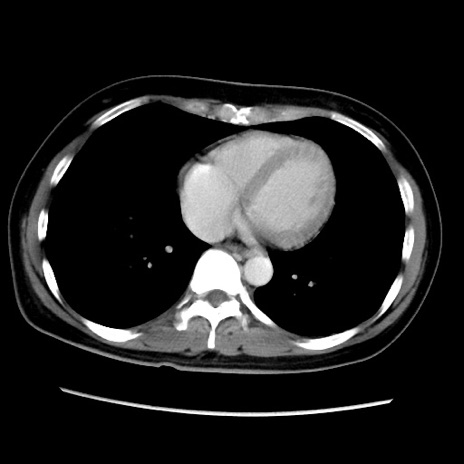

症例39(横断像)

【症例】40歳代女性

【主訴】上下腹部痛

【現病歴】2日目から下腹部痛あり。夜間は痛みで眠れなかった。昨日より上腹部痛と下痢が出現。臥位で痛みは軽快したため、休んでいた。本日になって臥位でも立位でも痛みが強くなってきたため救急要請。

【既往歴】子宮内膜症

【身体所見】部:平坦・軟、左上下腹部に圧痛あり、反跳痛あり。

【データ】WBC 21800、CRP 26.78